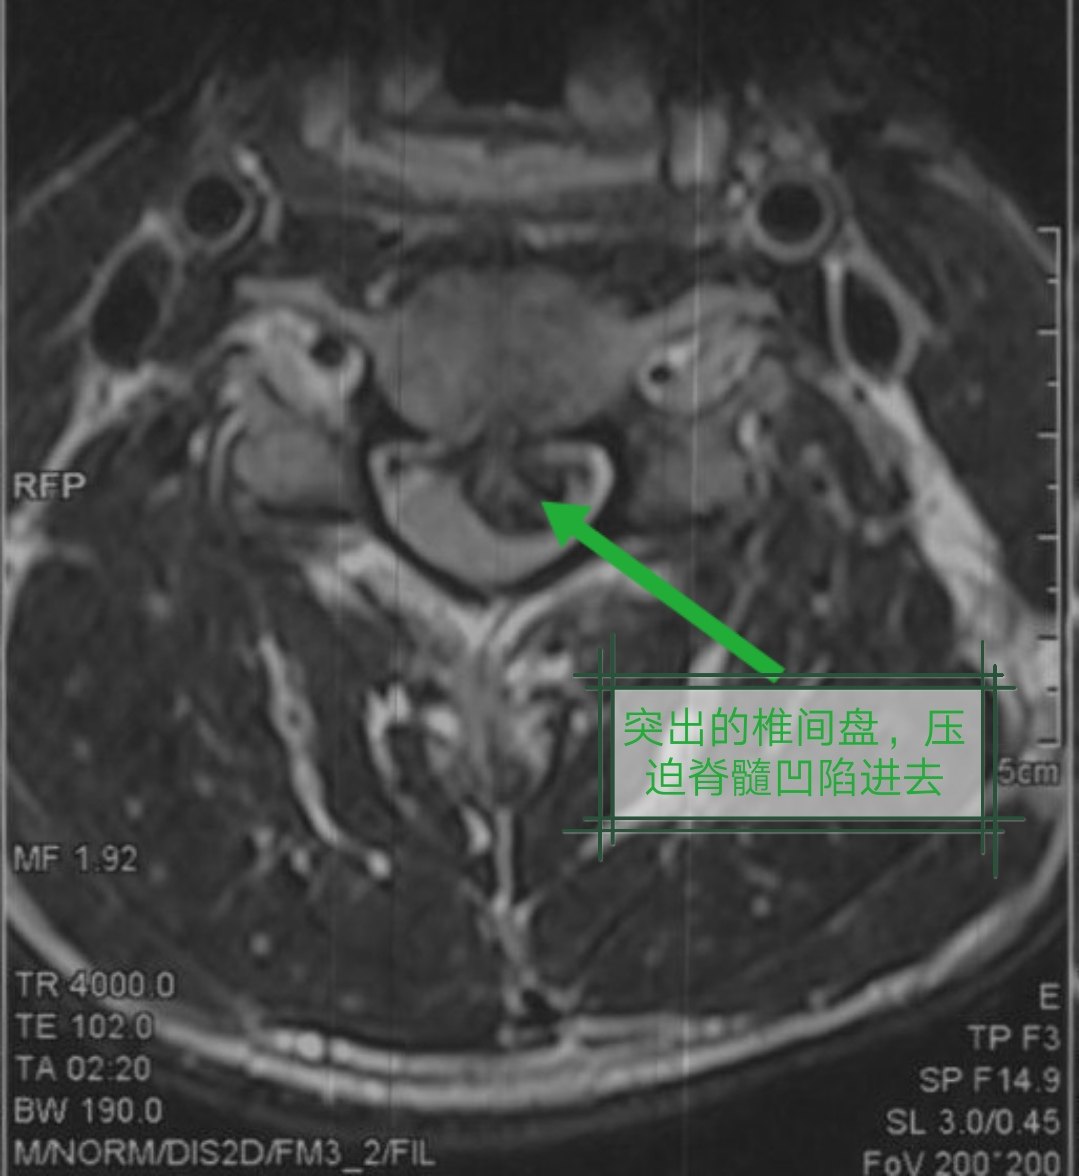

① 神经根型颈椎病的患者,症状主要表现为一侧颈部和胳膊疼痛,上举后疼痛减轻。颈椎MRI显示椎间盘突出偏向一侧,压迫神经根(图4)。

②脊髓型颈椎病的患者,症状主要表现双侧上肢疼痛麻木,无力,拿东西困难容易掉,走路无力,有踩棉花感。颈椎MRI显示:颈椎间盘突出,压迫脊髓导致局部椎管狭窄,白色脑脊液消失(图5—1)。而正常颈椎椎管可见脊髓漂浮在脑脊液内(图5—2)。